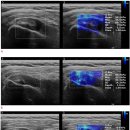

Re: shear wave elastography를 이용하여 극상근 건 파열 만성도 진단 2020 2025.07.10해당카페글 미리보기

영상법(shear wave elastography, SWE)이 사용될 수 있는지 조사했습니다. 방법 회고적 연구가 수행되었습니다. 2015년 11월부터...79세)의 환자가 일상적인 B-모드 초음파 검사를 통해 회전근개 건 검사를 받았으며, SWE를 사용하여 SST 탄성을 측정...